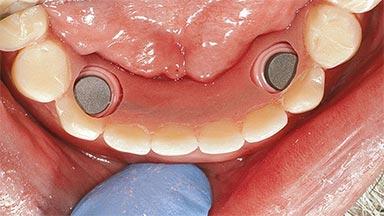

# of Implants 2

Type of Implants One-Piece

Attachment One-Piece

Defining Characteristics Fully edentulous lower jaw to be rehabilitated with two or more implants

Modality 2 interforaminal implants